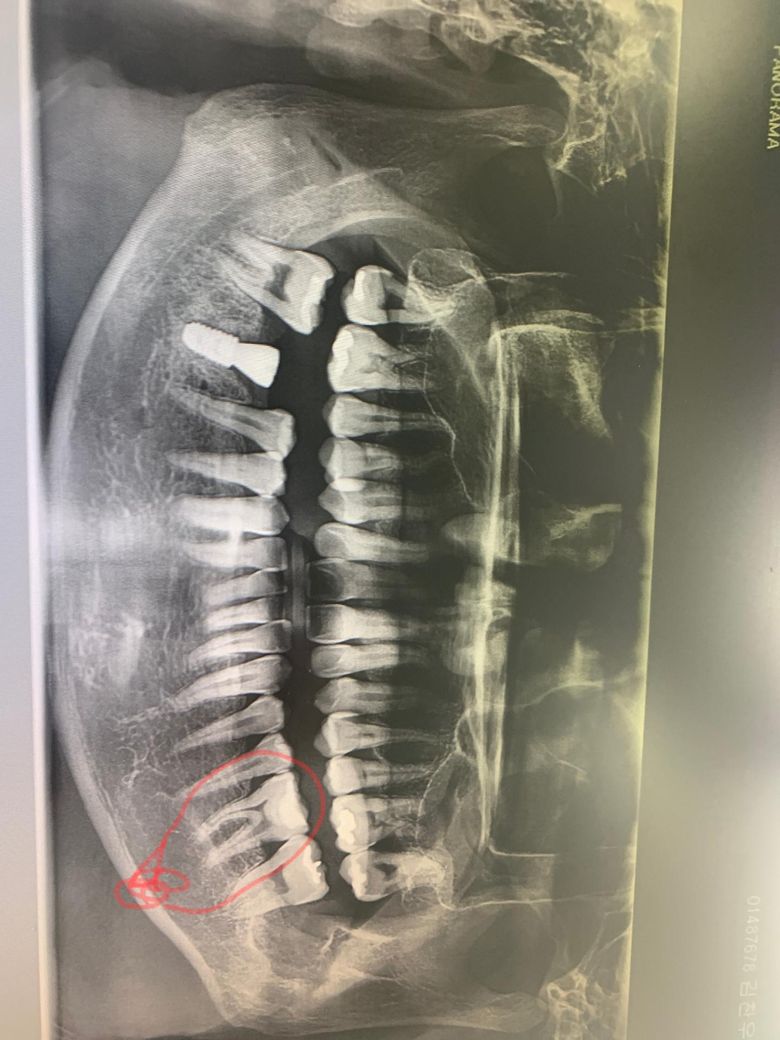

이 사진에서 신경치료해야할 이빨이 있나요

음식씹을때 한번씩 전기통한듯 강한 찌릿함과 통증이 있거든요 엑스레이파노라마 사진상으로 치료해야할 이빨과 살명부탁드립니다

사진으로 봤을 경우에 신경 치료를 할 정도의 큰 충치를 가진 치아가 보이진 않습니다. 하지만 치아에 금이 가서 통증이 생기는 경우라면 신경 치료를 하는 것이 좋을 수 있습니다.

엑스레이 사진상으로는 보이지 않지만 씹을 때마다 통증이라면 눈에 보이지 않는 금이 있을 수 있습니다.

사진상으로는 충치가 심하거나 그래 보이는 치료는 없지만, 증상이 잇거나 급성치수염이 잇어서 통증이 잇다면 치료를 해야될수도 잇습니다.

지금 사진은 panorama 사진으로 치아의 세부적인 사항을 모두 알기에는 어려움이 있습니다. 현재 사진과는 임상 검사와 병행해야 하며 필요시 PA나 dental-ct 등을 촬영해야 합니다. 현재 느끼는 증상은 치아의 금이 갔을 가능성도 있어 지속적으로 통증이나 불편감이 있다면 신경치료를 해야할 수도 있습니다.

1. 엑스레이 사진상으로 오른쪽 위 (그러니까 실제 방향은 왼쪽 위) 어금니 2개가 상태가 좋아보이진 않습니다만 신경치료가 필요할지는 치근단사진(작은 엑스레이 사진)을 찍어봐야 합니다

2. 다만, 증상으로 봤을때는 아마도 어금니에 크랙이 생긴 것 같습니다. 이런 경우 신경치료+크라운은 불가피합니다.